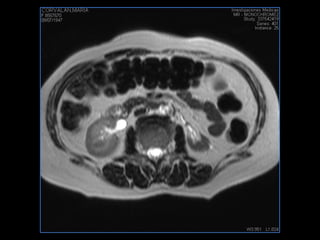

PROTOCOLO pelvis SAG T2, Y FAT SAT (FINOS) AXIAL T1  AX FAT SAT CON   GADOLINIO :  AX T1 Y COR T1 SAT: NO  FASE: RL THK: 3MM  COIL:  GAP: (FACTOR 1.4) 1MM FOV: 40 CM NEX:2 SINCRONIZACION RESPIRATORIA EN 3 O 4 CICLOS ALE

resonancia de abdomen